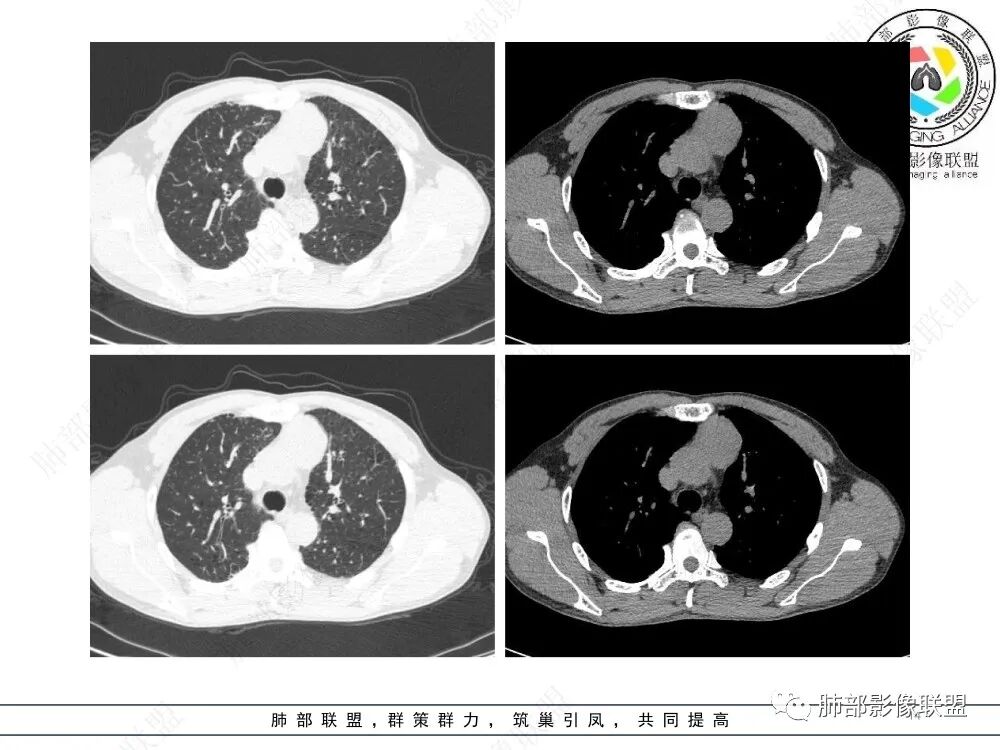

放射小白:男性47岁,前纵隔团块状占位,边界尚清,增强中度强化,内部疑似纤维分隔,常规考虑胸腺瘤可能(A/AB型),鉴别类癌、CD。

瑞欣:中年男性,检验未见明显异常,前纵隔软组织快影,边界清,可见明显强化,首先考虑胸腺瘤,鉴别淋巴瘤,畸胎瘤,生殖细胞瘤。

金豆:晨读:定位前纵隔,膨胀性生长,质地中等,边界清,有浅分叶,中等强化,似乎有裂隙低密度,常规胸腺瘤(B1)。

Yishion:晨读:纵隔占位,偏侧生长,边界清楚,有浅分叶,强化明显,其内似见纤维分隔,常规考虑胸腺瘤(AB型)。

蓝天白云:晨读:47岁男,前纵隔占位,边界清,有浅分叶,中等强化,胸腺瘤(B1)。

宇宙:前纵膈偏左类圆形肿块,边界清晰光整,与大血管脂肪间隙清,密度均匀,轻中度强化,考虑胸腺瘤,A型?鉴别胸腺癌。

玫:男,47岁,咳嗽,咳痰一年,前纵隔软组织密度肿块影,边界清晰,内密度均匀,增强扫描轻度强化,考虑胸腺瘤可能。

周太狼:中年男性,前上纵隔胸腺区软组织团块占位,边界清,增强中度强化,内密度较均匀,常规考虑胸腺瘤。

月亮圆了!:前纵隔包块,边界清,有分叶,密度不均,中等强化,考虑胸腺瘤。

衡妈🇨🇳:中年男性,前纵隔偏左侧实性占位,密度相对均匀,边缘分叶,周围脂肪结构略模糊,增强后动脉期不均匀强化,有低密度区,纤维分隔显示不清。考虑胸腺瘤B1 B2型。

朱伟超:中年男性,前纵膈偏离中线肿块,浅分叶,内有分隔,中等不均匀强化,常规胸腺瘤。

流心明智:男,47,咳嗽、咳痰1年余。胸部CT:前纵膈偏左类圆形肿块,瘤肺界面清晰光整,纵隔侧部分层面絮状影?平扫密度较均匀,增强后轻度强化,内可见宽带及线样低密度分隔。邻近左上肺受压凹陷。考虑胸腺肿瘤,AB型?胸腺Ca?鉴别淋巴瘤、N源性肿瘤、CD等。

2、影像特点:前纵隔偏左侧软组织影,密度相对均匀,未见明显包膜钙化及实质内钙化,局部边缘浅分叶,周围脂肪间隙密度增高、浑浊,未见侵犯大血管、未见纵隔内淋巴结转移、未见侵犯心包内结构、未见胸膜转移结节、未见肿块沿着纵隔胸膜蔓延,未见胸腔积液。增强后动脉期不均匀强化,未见明显纤维分隔。